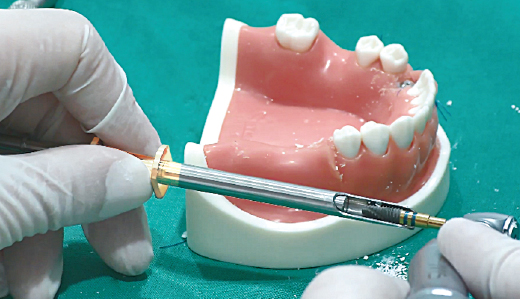

주사기로 rhBMP-2 용액 흡입

1. Bone Carrier의 원형 홈에 먼저 rhBMP-2 용액을 주사

-